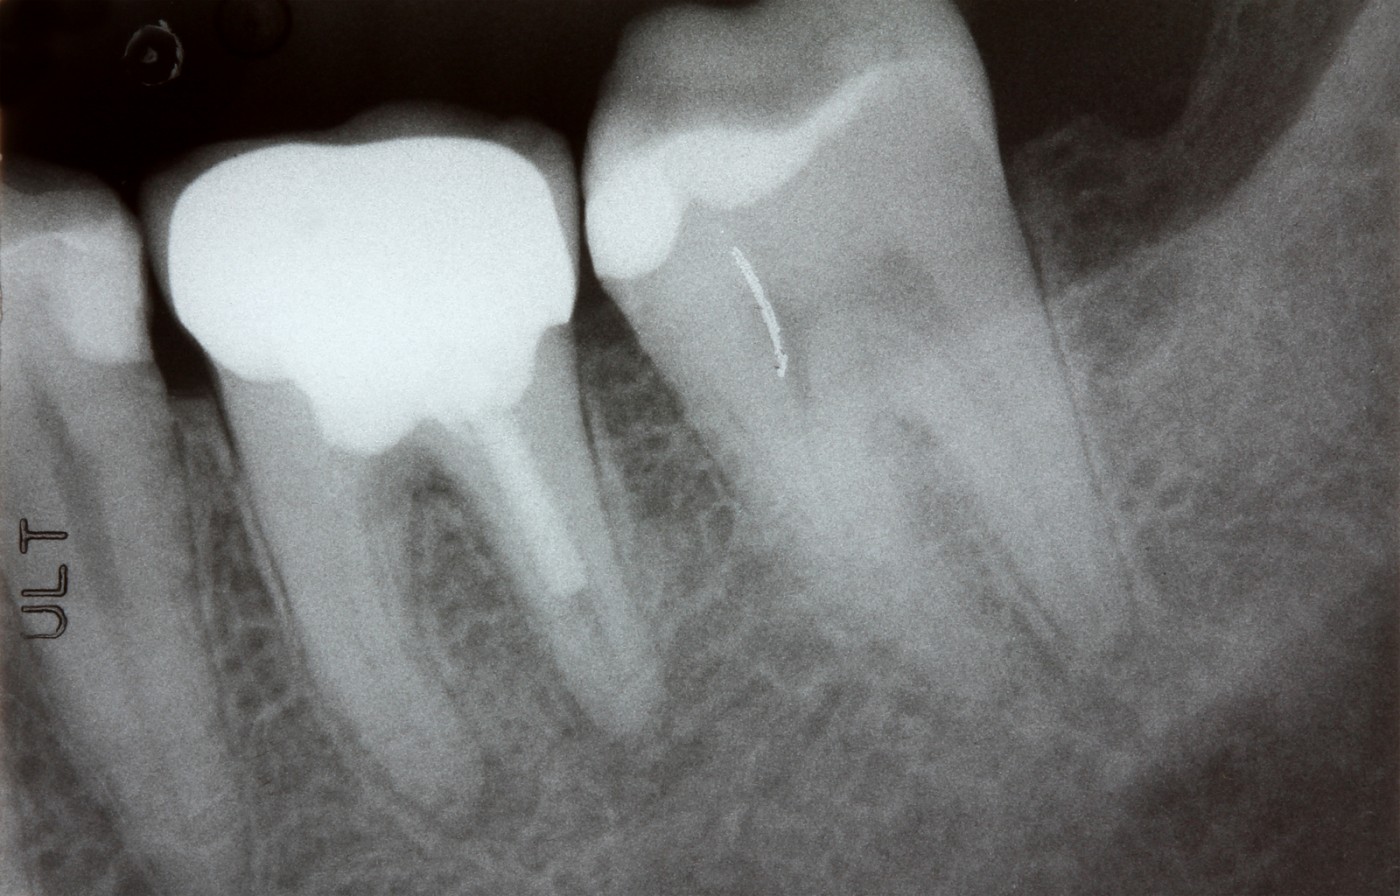

Cea mai des utilizată radiografie dentară intraorală este radiografia retroalveolară digitală, denumită și „periapicală ”. Aceasta surprinde doar imaginea detaliată a maxim 3 dinți.

- Imagine detaliată a dintelui, în întregime (vizează coroana, rădăcina și osul în care aceasta este ancorată);

- Înaintea tratamentelor endodontice, pentru stabilirea numărului de canale radiculare, a morfologiei și lungimii acestora;

- După tratamentele endodontice, pentru evaluarea corectitudinii acestora;

- Determinarea profunzimii proceselor carioase;

- Detectarea cariilor secundare și a celor recidivante;

- Diagnosticarea de chisturi, granuloame;

- Localizarea și monitorizarea dinților incluși;

- Depistarea fracturilor coronare, radiculare.